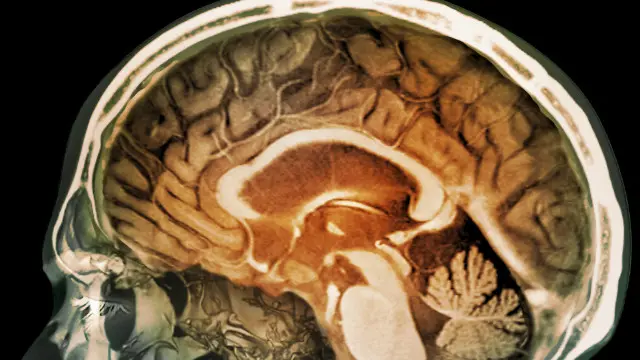

آلودگی کے ذرّات کی انسانی دماغ تک رسائی

ایک نئی تحقیق سے پتا چلا ہے کہ دماغ کے ریشوں کے بعض نمونوں میں آلودگی کے باریک ذرّے ملے ہیں۔

نئی تحقیق سے پہلی بار ایسے شواہد ملے ہیں کہ آلودگی دماغ تک رسائی حاصل کر لیتی ہے۔

،تصویر کا ذریعہScience Photo Library